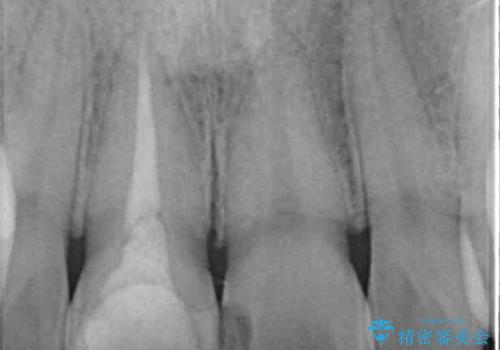

- 事故でぶつけて神経を取り除いた歯が変色したとのことで来院された患者様です。

処置直後は欠けた部分を詰めた材料で見た目に問題なかったそうですが、年々変色してきて、かなり目立つようになっていました。

根管治療された状態に大きな問題はなかったため、土台を植立し、オールセラミッククラウンにて補綴治療を行うこととしました。